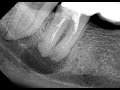

Индекс Р основывается на оценке различных параметров: глубины карманов зондом, кровоточивости десен, наличия зубного налета и зубного камня. Чем выше индекс Р, тем более выраженное состояние пародонта и большая потребность в лечении.

Оценка индекса Р обычно проводится стоматологом при помощи специального инструмента - пародонтального зонда. Пациентам рекомендуется регулярно проходить профилактические осмотры у стоматолога для контроля состояния пародонта и своевременного выявления проблем.